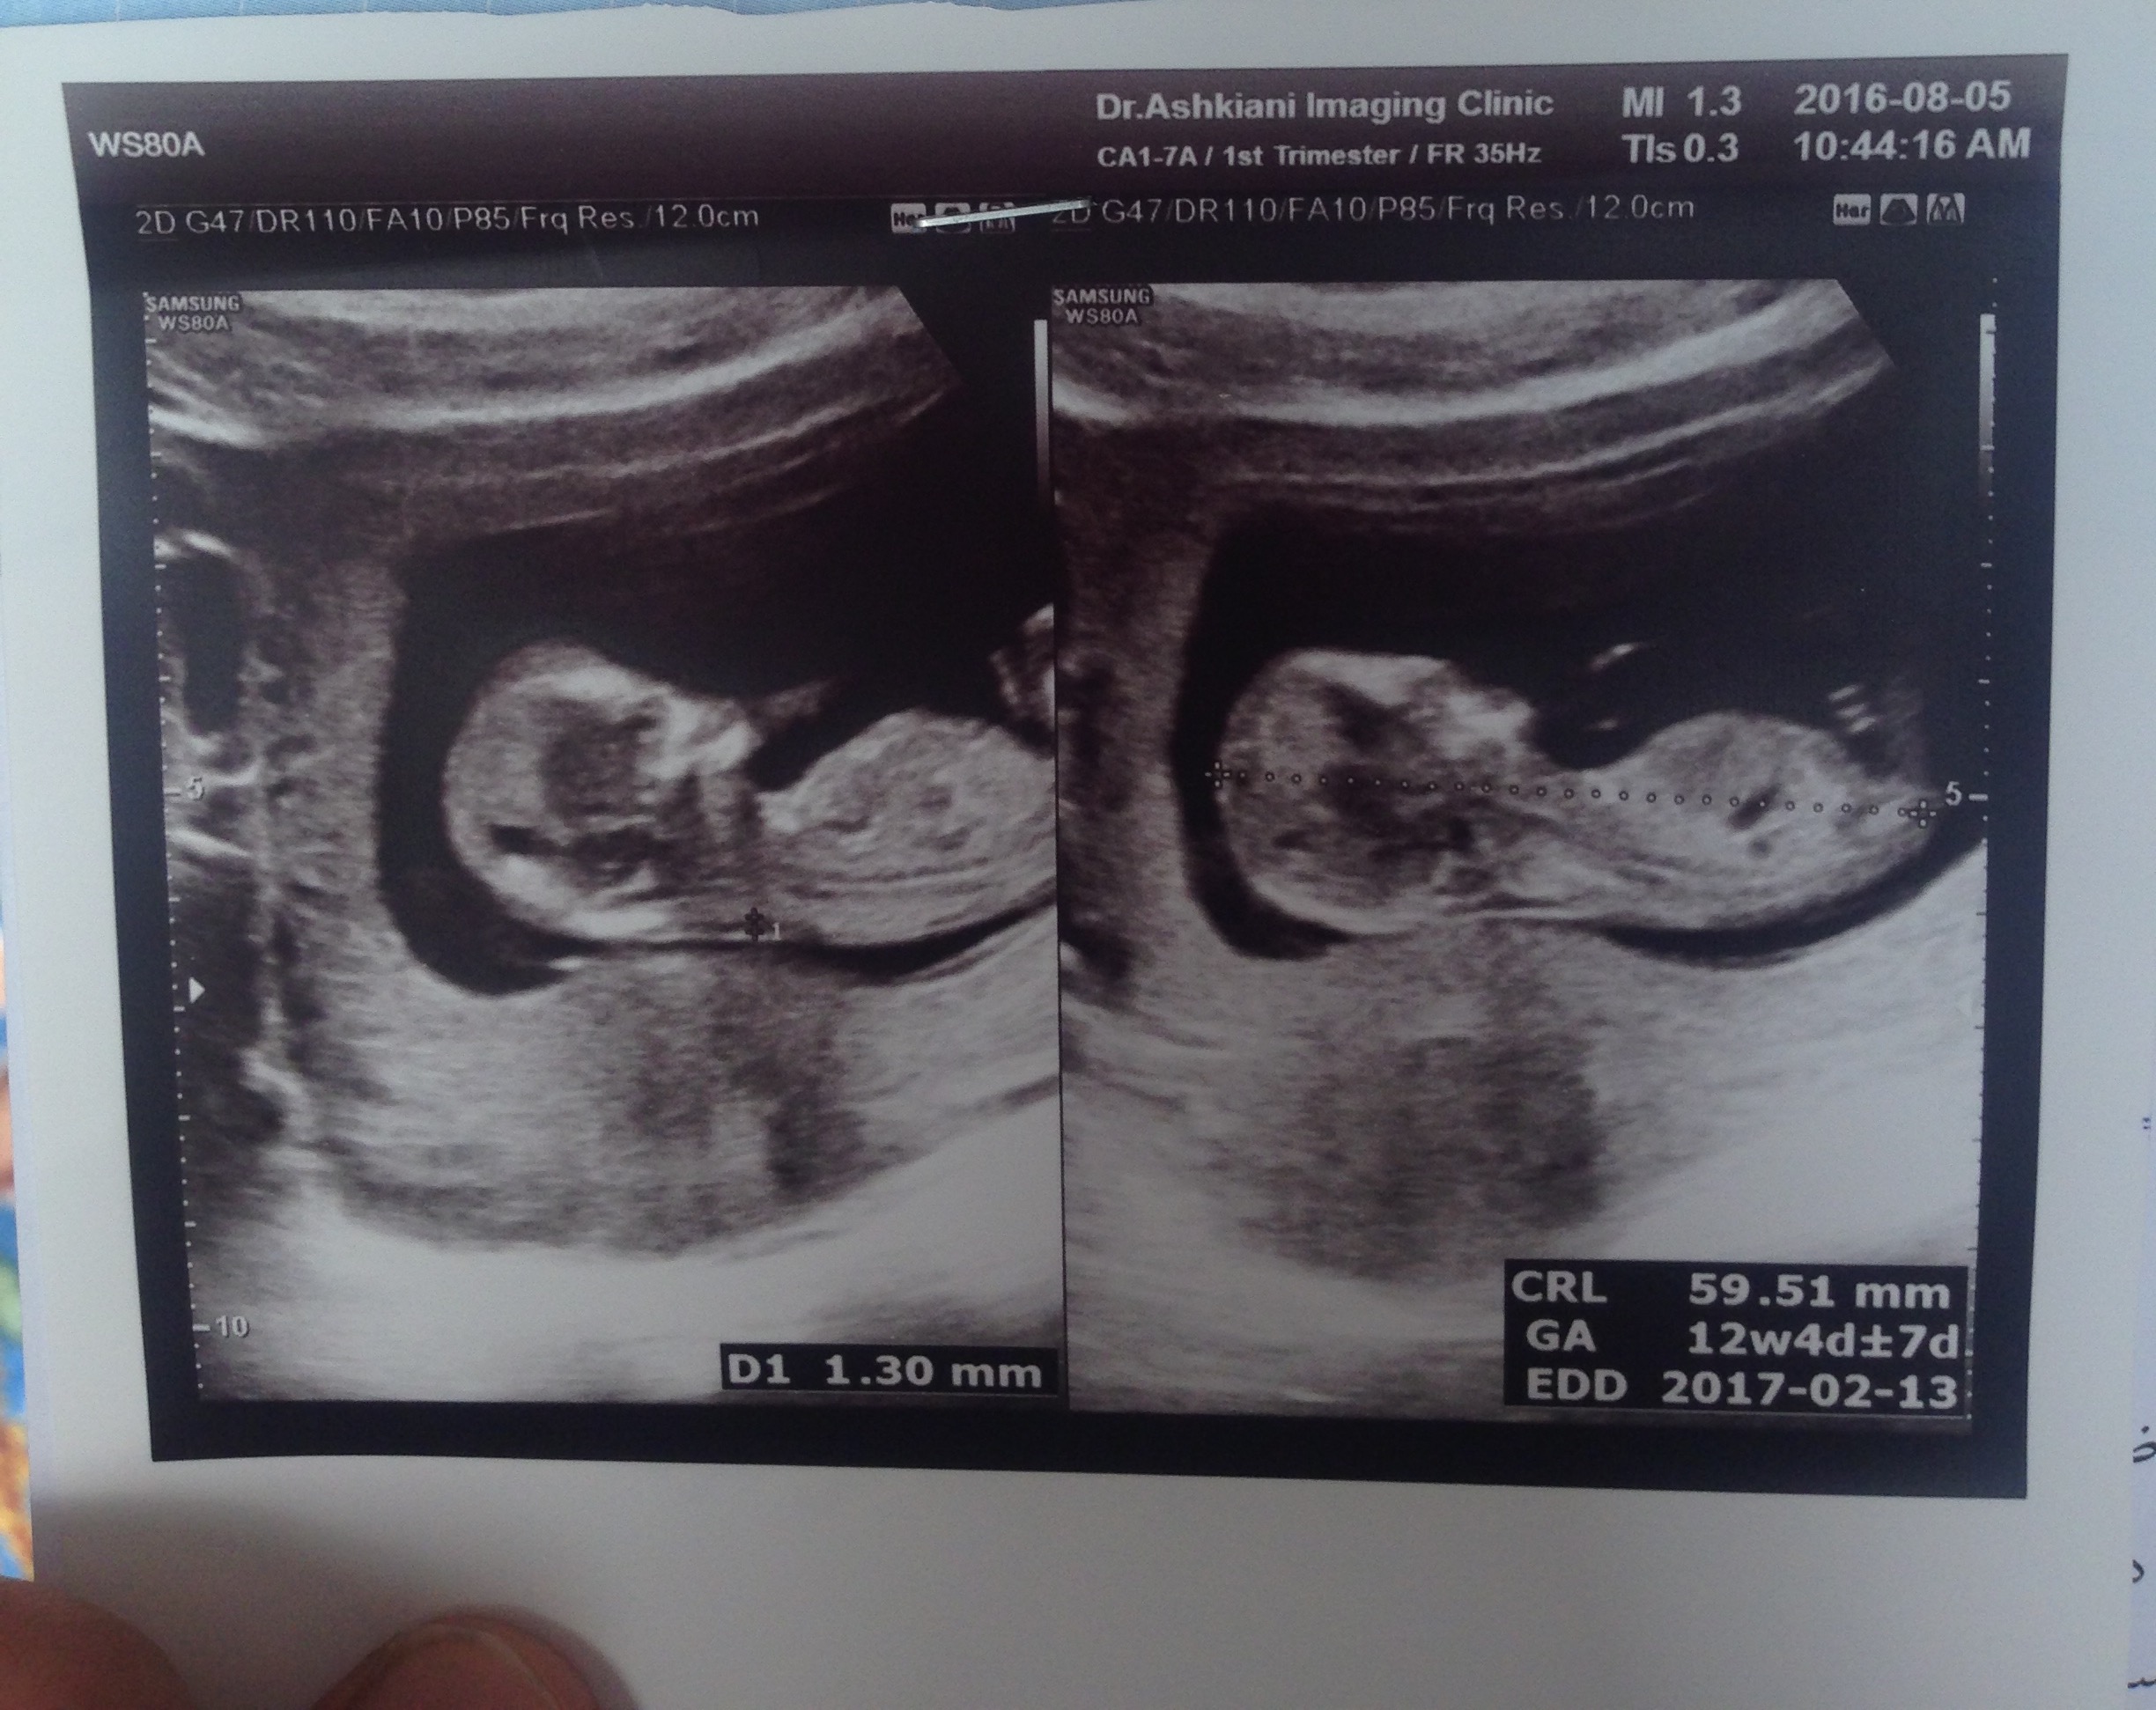

ببین عکسمو بچرخون ...چرخید تو گذاشتن ... این عکس ساک حاملگیمه تو هفته ۷ ... ببین جنین یا همون چیزی که قراره جنین بشه سمت چپ پایینه ... چپ پایین خود ساک ... نه رحم ... یعنی ممکنه دختر سمت راست رحم هم باشه یا پسر چپ رحم ... ولی اون جوجوی تو ساک باید ببینیم متمایل به چپه ساکه یا راست ساک حاملگی